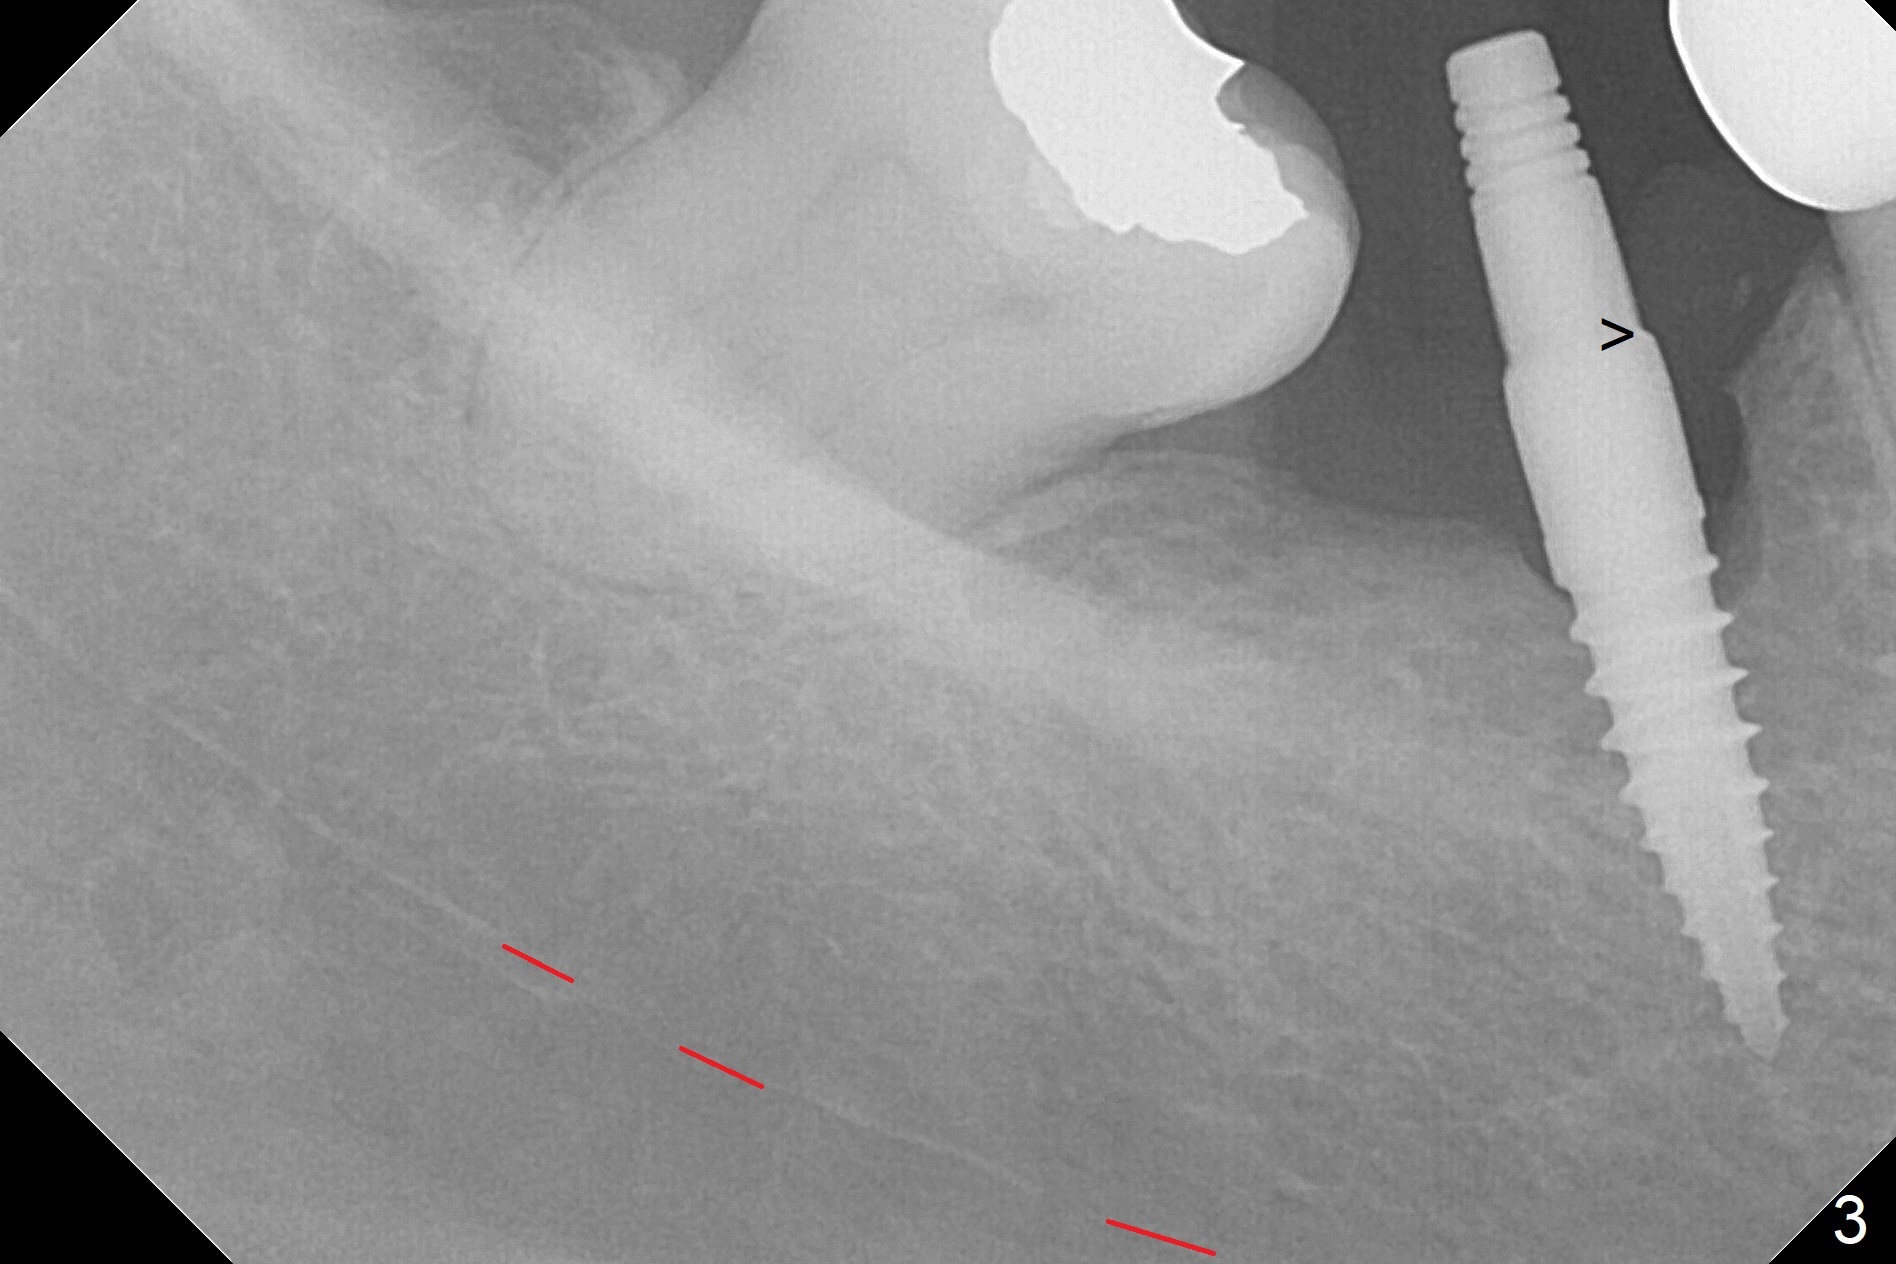

1-Piece Implant at Molar with Narrow Ridge

Incision reveals a narrow ridge and a narrow mesiodistal space at #30 (Fig.1). It seems that a 1-piece implant is indicated. Due to limited mouth opening, a 1.2 mm drill is unstable in place after use for 10 mm; instead a 1.5 mm drill is able to be inserted for 8 mm (Fig.2). A 3x10(2) mm 1-piece dummy implant is placed with 40 Ncm at an apparently acceptable level (Fig.3 >). Clinically a few threads are exposed buccally. When a definitive implant with the same dimension is inserted with 45 Ncm, it looks seated too deep (Fig.4,5). The latter is noted after suturing. The implant is backed up for a few turns so that the length of the abutment appears a little more reasonable. Introspectively, a 4 mm cuff should have been used after ridge reduction. Although there is no bone loss 4 months postop (Fig.6), the abutment margin (Fig.7 arrow) is subgingival (red dashed line: gingival margin). Diode laser is used for gingivectomy prior to impression. The bone density around the implant increases 11 months post cementation (Fig.8 *), probably related to recurrent #18 infection. The patient uses floss after meal.